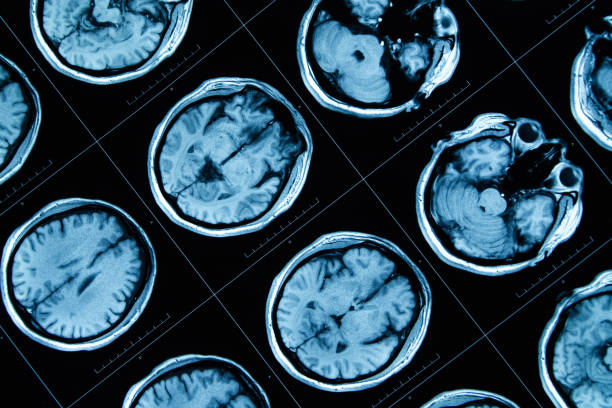

8.干細胞治療神經系統疾病

干細胞治療帕金森病:帕金森病是一種神經退行性疾病,主要由多巴胺能神經元的喪失引起,導致運動功能障礙。

《醫學前沿》期刊的一項系統綜述顯示,全球采用間充質干細胞(MSC)治療神經系統疾病的43項臨床試驗,包括30項I期、7項II期和6項I/II期試驗,研究結論表明干細胞MSCs被認為是一種安全且耐受性良好的療法。在帕金森病的臨床試驗中,干細胞移植顯示出再生多巴胺能神經元的潛力,顯著改善了患者的運動功能,緩解了帕金森病的癥狀。【數據來源:TheLancetNeurology】。